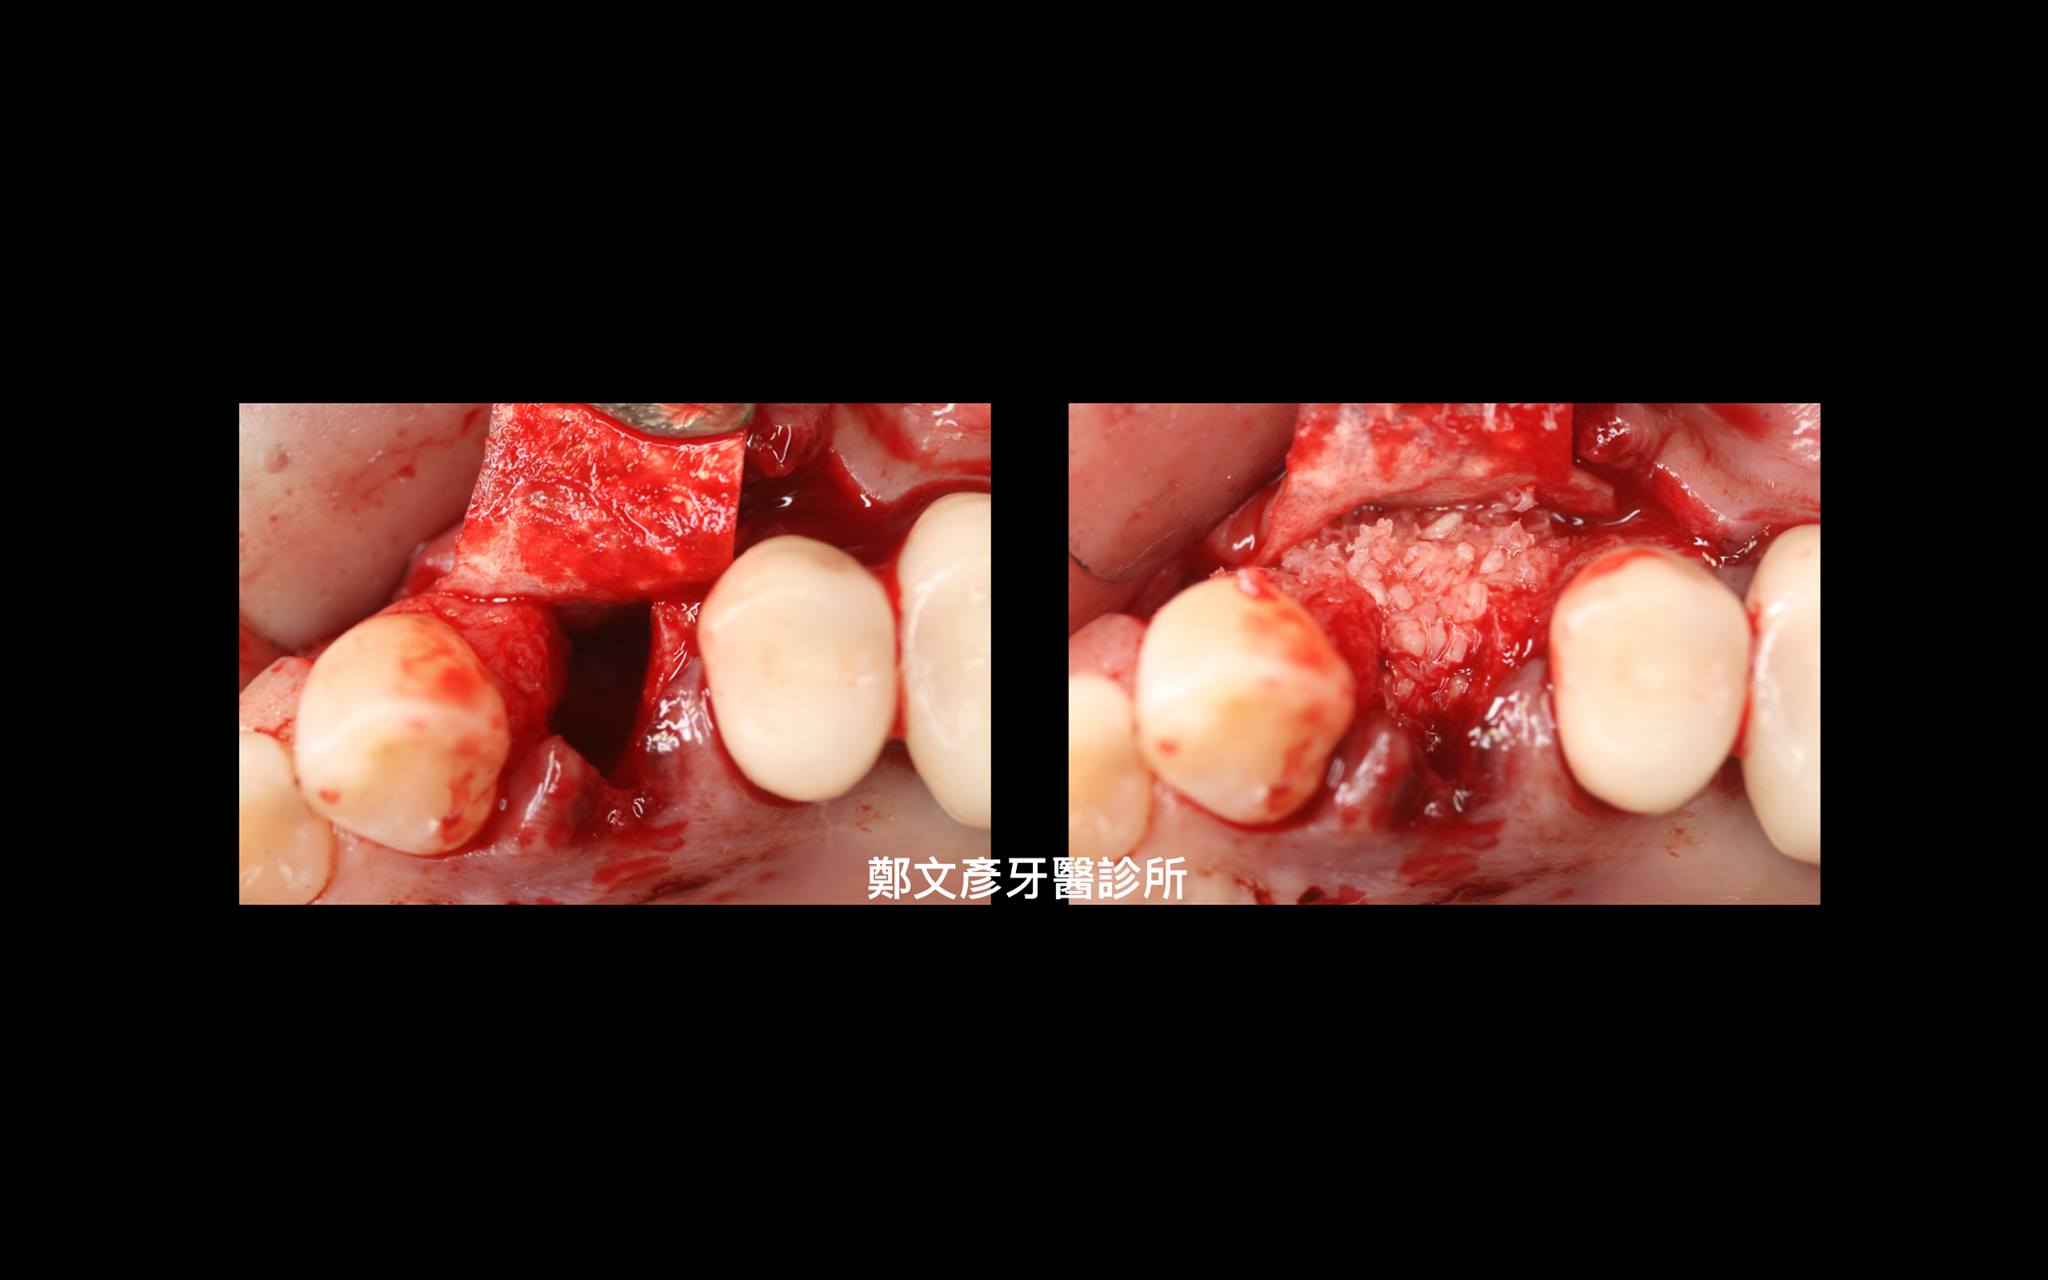

3. Role of granulation tissue in socket preservation

Role of granulation tissue in socket preservation